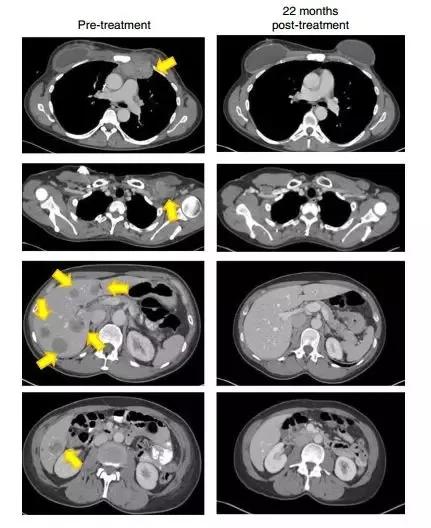

22个月后,我的影像检查显示(黄色箭头)肿瘤消失得无影无踪(图片来源:《Nature Medicine》)

看到旁边的医护人员“一个个都兴奋地蹦达了起来”。我就知道,我赢了。